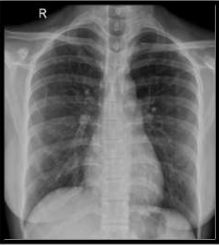

She was started on intravenous cyclophosphamide. However since there was not much improvement in oxygenation and persistent lung infiltrates, after multidisciplinary discussion she was given 7 cycles of plasmapheresis and IV Rituximab. She gradually improved clinically , her serial chest x rays showed improvement , oxygenation improved and was eventually decannulated from ECMO on day 7.Sedation was slowly withdrawn , her GCS improved and she was gradually weaned off from ventilator support over next 5 days. She was mobilised, was given adequate chest and limb physiotherapy and was shifted to ward on minimal oxygen support over next 5 days. Eventually her oxygenation improved and she was discharged without oxygen support with tapering steroids and PCP prophylaxis. She had followed up at OPD and was free of symptoms, chest x ray showed significant improvement with complete clearing up of parenchymal infiltrates. Below are the serial Chest X rays taken during the course of hospital admission and follow up.